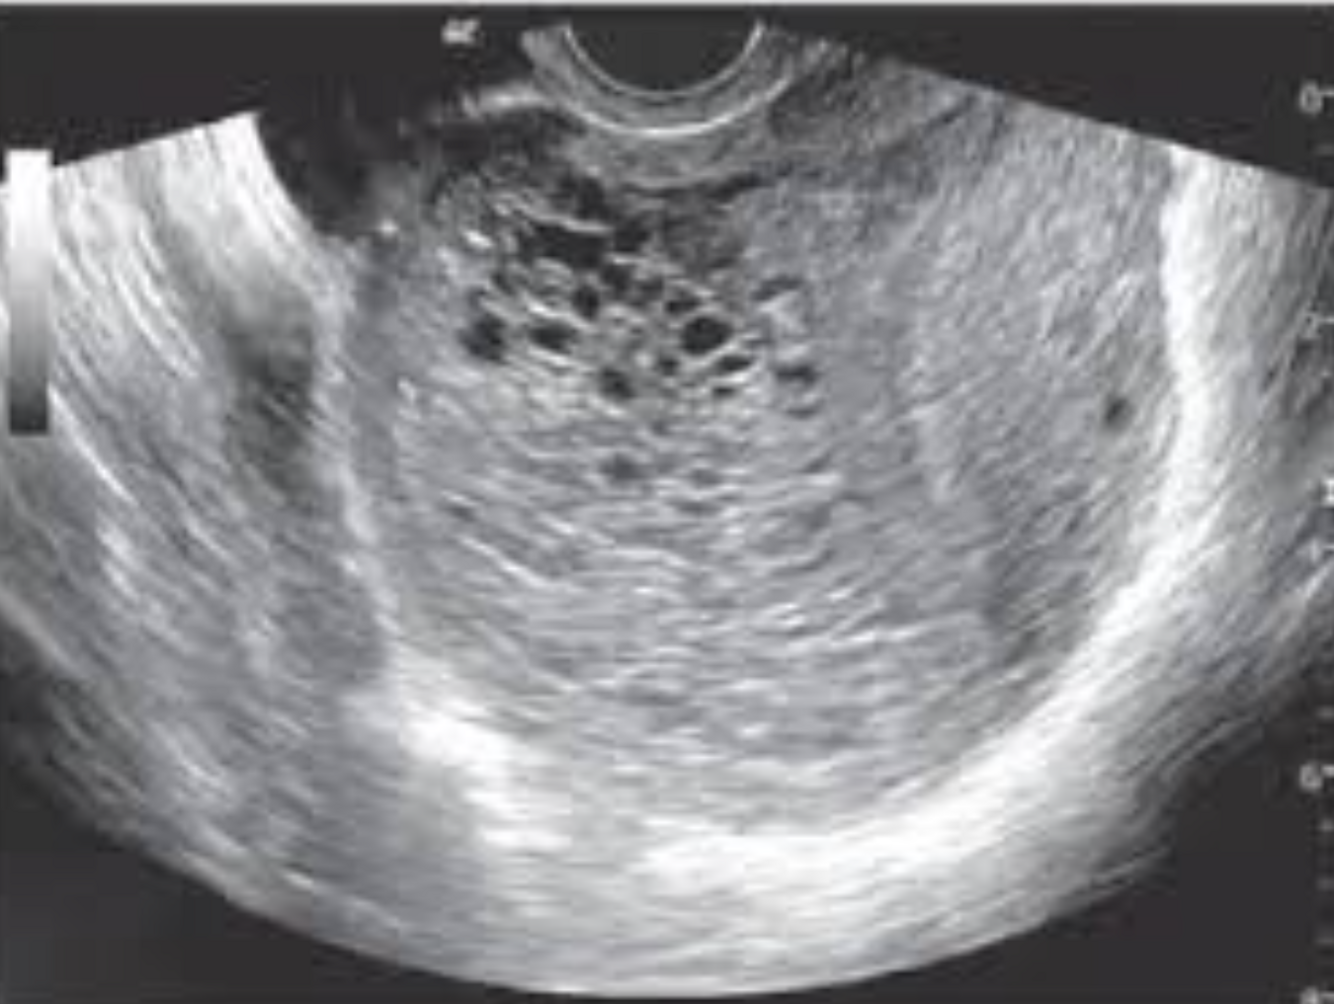

Imagem USG característica de mola

Imagem em flocos de neve ou cachos de uva